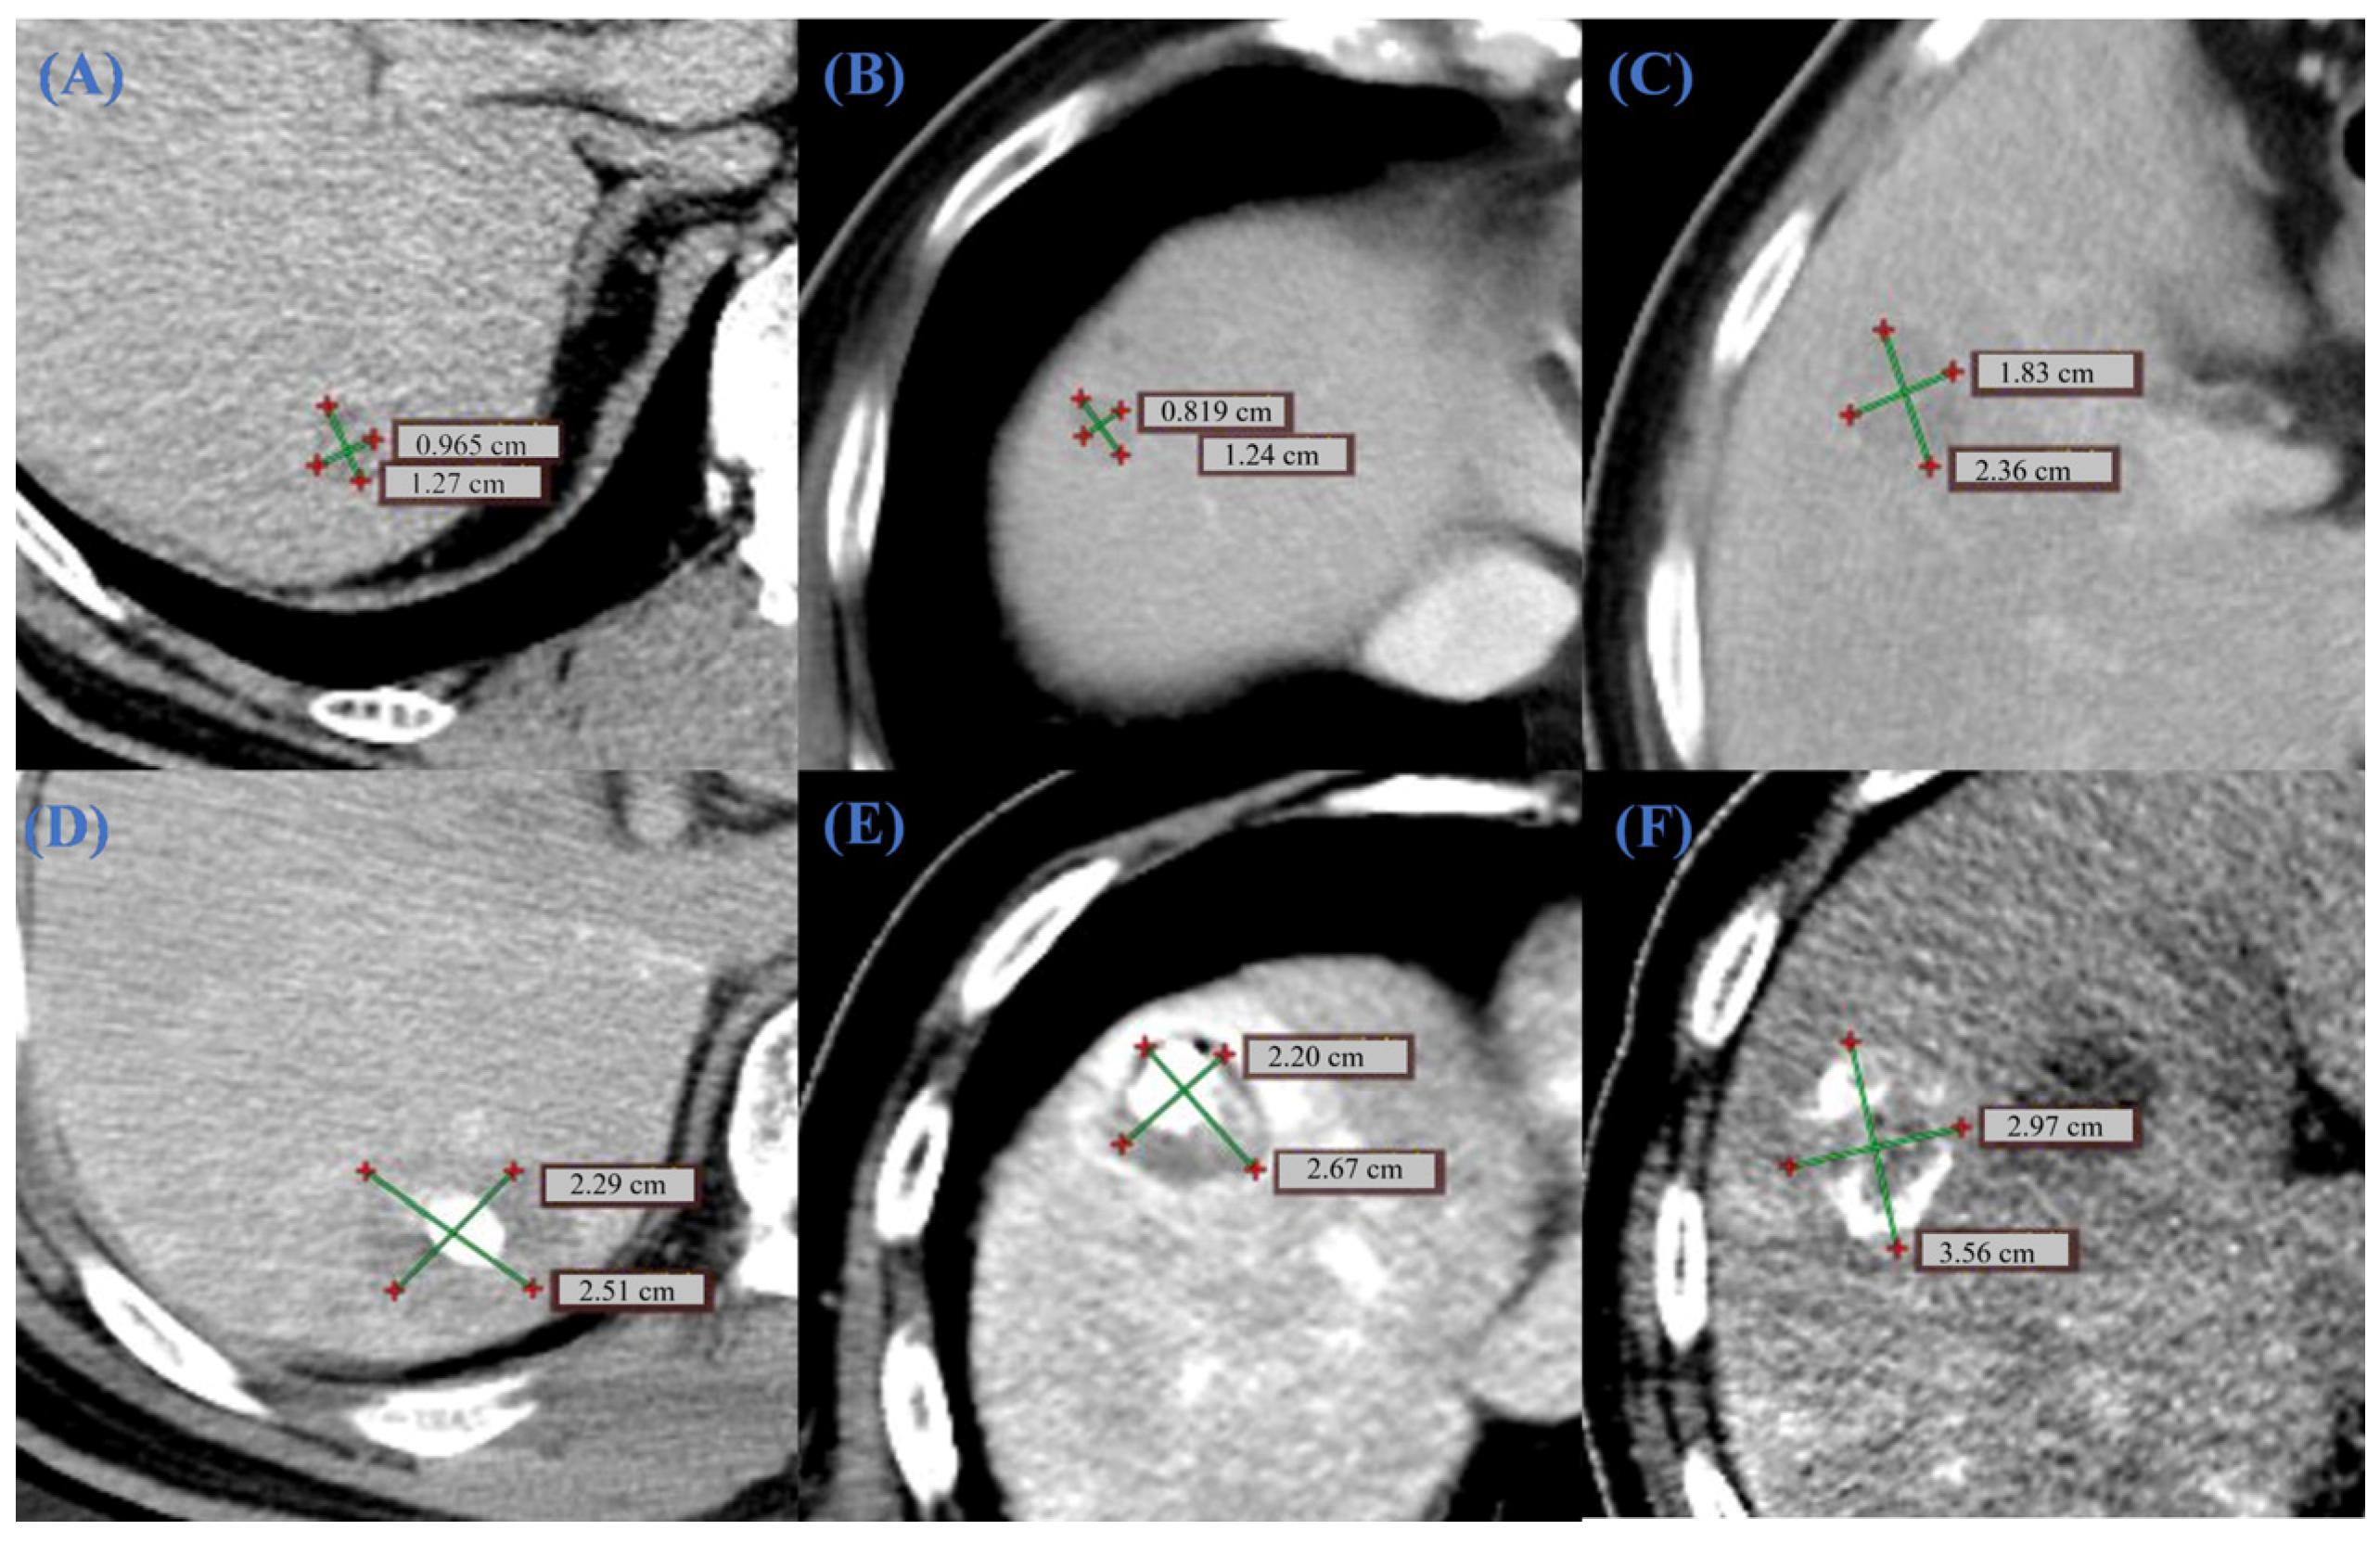

The clinical data in this study were obtained from enhanced CT scans of two patients with liver tumors at Beijing You’an Hospital, affiliated with Capital Medical University (Table 2). The study has been approved by the hospital’s ethics committee and informed consent has been obtained from the patients. All image data has been anonymized and complies with medical data protection regulations. The physicians first used version 5.4.0 of the 3D Slicer software [24] to complete CT image segmentation (Figure 1). Then they generated STL models of the liver and tumors through surface reconstruction algorithms for subsequent COMSOL simulation analysis.

3.2.2. CT Image Analysis

In clinical surgery, CT scans play a crucial role in determining the ablation needle insertion point and in achieving surgical navigation [41]. To ensure a rigorous evaluation, the superiority of the OMWA strategy was assessed by comparing simulated OMWA outcomes against simulated single-needle outcomes under identical anatomical and physiological constraints. Retrospective clinical data (Figure 9) were presented independently to illustrate the clinical implementation of the OMWA strategy. To verify the clinical applicability of the proposed simulation method, Figure 9 illustrates the clinical effects before and after treatment in two representative patients. Patient 1 had a preoperative tumor length of 1.27 cm (Figure 9A). After ablation, the coagulated necrotic area expanded to 2.51 cm (Figure 9D), and imaging confirmed that the coagulated area completely covered the tumor. For patient 2, whose tumor morphology was more complex, multi-slice CT observation showed preoperative tumor diameters of 1.24 cm and 2.36 cm (Figure 9B,C). Immediate follow-up images after MWA (Figure 9E,F) showed significant morphological changes in the tumor area. The coagulated area measurements reached 2.67 cm and 3.56 cm, respectively. Quantitative analysis indicated that the postoperative ablation area was significantly larger than the original tumor volume, successfully establishing an ideal safety margin and ensuring effective local tumor control.

Figure 1. Schematic diagram of segmentation results for clinical patient liver CT images.

Figure 9. Comparison of tumor CT images before and after clinical surgical treatment. (AC) shows the preoperative tumor size. (A) represents the CT image of patient 1, and (B,C) represent the CT images of different lesions in patient 2. (DF) correspond to the immediate postoperative images at the aforementioned locations. The crosshairs in the images mark the long-axis and short-axis (cm) of the lesion and the postoperative coagulation zone. The comparison shows that the postoperative coagulation necrosis zone significantly exceeds the original tumor boundary, and both its long and short axis measurements are greater than the preoperative tumor morphology, confirming that the coagulation zone completely and effectively covered the target tumor. The green crosshairs indicate the measured axes of the lesion or coagulation zone, and the red markers denote the endpoints of the measurements.